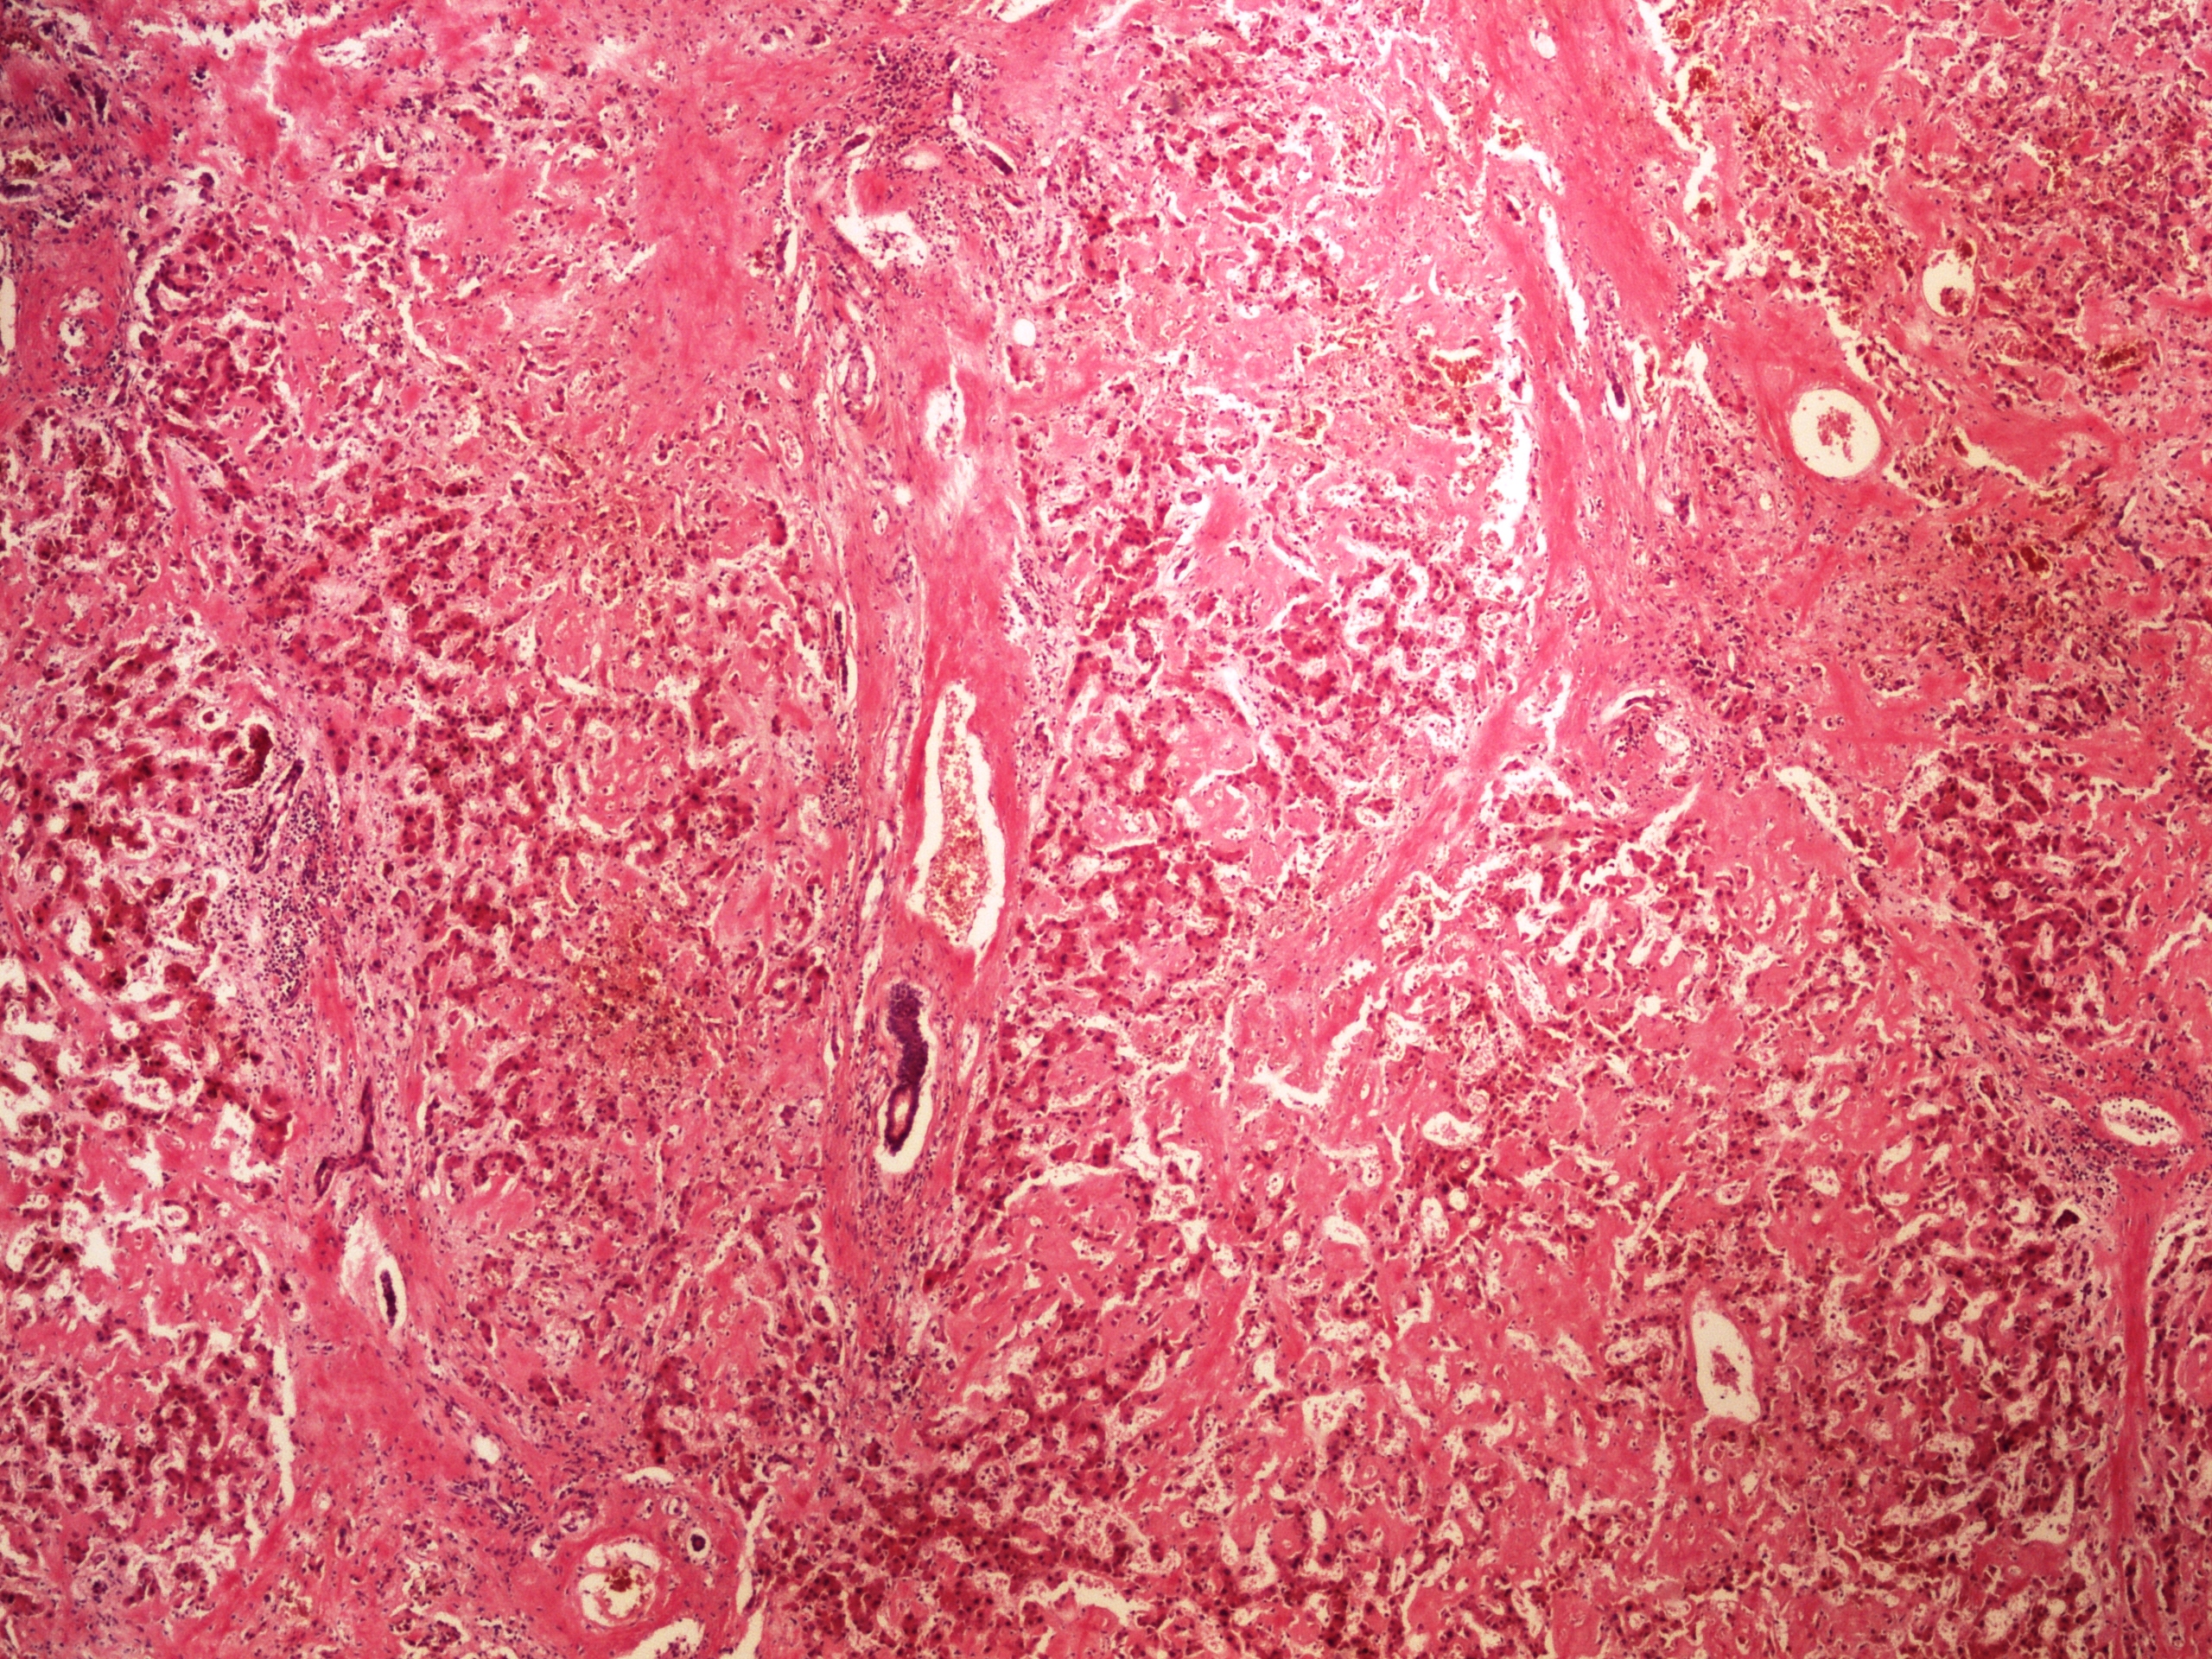

Амилоидоз внутренних органов при туберкулезе - фото презентация